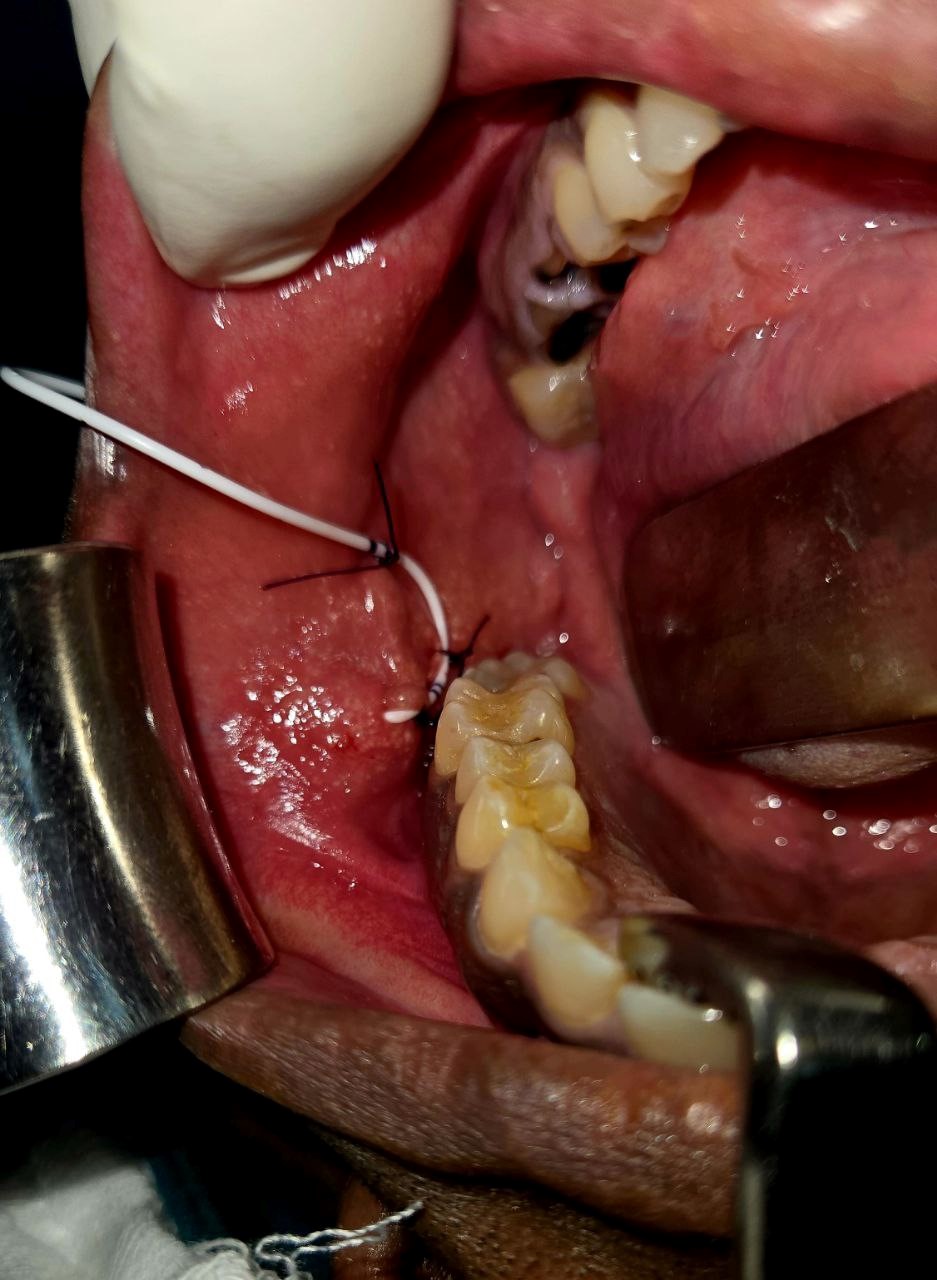

- Hemostasis was achieved. Duct integrity was confirmed by expressing saliva through the stent.

- Closure was performed over a Surgicel pack in two layers using 4-0 Vicryl.

- The patient tolerated the procedure well. There were no signs of sialocele, ductal leak, infection, or facial weakness. The DJ stent was retained in situ for 7 days to maintain ductal patency and then removed without complication.